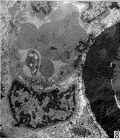

2.2 电镜观察 50 V神经损伤组:2 wk时,镜下观察无髓神经纤维有部分的空泡形成, 表现为轴突内微丝、微管等细胞器消失,呈低密度均质状态(Fig 1). 微血管内壁光滑,管腔无闭塞及栓塞(Fig 2),雪旺氏细胞轴突复合体无明显改变. 1 mo时,有髓神经、无髓神经结构已恢复正常,空泡现象消失,雪旺氏细胞形态正常. 3 mo时,神经结构未发现异常. 75 V神经损伤组:2 wk时,受损的神经纤维数目明显增加,损伤程度加重. 表现为无髓神经纤维轴膜破裂,轴浆外溢. 有髓神经纤维板层开始解体(Fig 3). 但微血管结构无明显变化. 仍可见到形态结构正常的神经纤维. 雪旺氏细胞形态无明显变化. 1 mo时,可见到新生的神经纤维,主要以两种形式存在. ①新生的神经纤维沿原有的溃变的神经膜管生长. 镜下可见到溃变解体的髓鞘内存有结构清晰的有髓神经纤维(Fig 4). ②新生的无髓神经纤维由雪旺氏细胞形成髓鞘逐渐包裹而成(Fig 5). 未得到神经再支配的神经纤维结构开始解体(Fig 6),无髓神经纤维轴膜破裂相互融合. 有髓神经纤维髓鞘厚薄不均,并溶解形成滴状结构. 3 mo时,再生的神经纤维结构进一步成熟. 可见新生髓鞘较薄,但外层光滑,亦可见到尚未完全形成包裹的板层髓鞘(Fig 7). 无髓神经纤维数目减少,但直径增大,雪旺氏细胞包裹的无髓神经纤维数目减少,并处于细胞的外层. 胶原纤维无明显增加. 200 V神经损伤组:1 wk时,镜下观血管内膜凹凸不平,管腔内有血栓形成(Fig 8). 无髓神经纤维变性,雪旺氏细胞数量减少. 有髓神经髓板全部呈松散结构,板层分离. 1 mo时,镜下观血管内膜凹凸不平加重,管腔完全闭塞. 胶原纤维含量开始增加. 雪旺氏细胞基膜与轴突分离,髓鞘厚薄不均,髓鞘板层松散呈丝瓜囊状(Fig 9). 3 mo时,镜下见胶原纤维含量明显增加,占据大部分视野. 无髓神经纤维消失,有髓神经纤维板层分离并皱缩成团,轴突管腔消失成为实心结构. 雪旺氏细胞结构消失.

图 8 血管内膜凹凸不平,管腔内有血栓形成

图 9 有髓神经纤维板层分离并皱缩成团